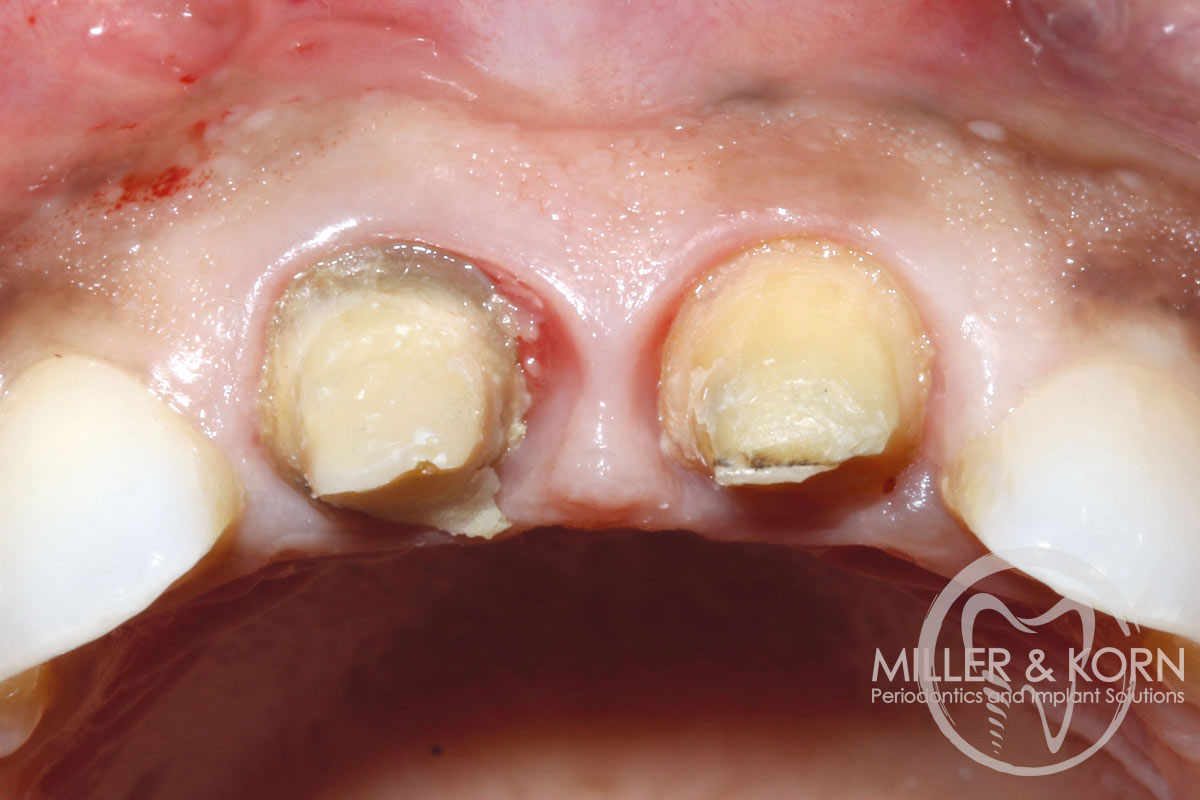

2/22 - She experienced trauma as a child and had fractured both tooth #8 and 9 which had been crown several times for esthetics.Immediate implant placement and regeneration of ridge using an allograft bone ring and Jason® membrane - Drs. Miller and Korn

60-year-old female patient presented with a chronic infection on tooth #11.

Since she has a high lip line matching the gingival margins of the adjacent central incisor and creating a root eminence is extremely important. For these reasons, the treatment of choice was an allograft bone ring enabling immediate placement of the dental implant with simultaneous regeneration of her ridge.